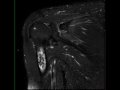

Bone Infarct, Humerus

58-year-old male who presents for chronic right shoulder pain. There is an infiltrative T1 hypointense, STIR heterogeneously hyperintense lesion centered within the proximal right humeral diaphysis with extension to involve the metaphysis. There is heterogeneous enhancement. There are central components of the lesion which are both T1 hyperintense and STIR hypo-intense compatible with internal fat. The lesion is centered within the medullary cavity without definite endosteal scalloping, cortical breakthrough, or associated soft tissue component. Imaging findings are most compatible with bone infarction. Bone infarct is secondary to interruption of blood supply to bone. A central necrotic core is established with a hypoxic peripheral zone. Causes include trauma, Caisson disease, hemoglobinopathy, radiation therapy, connective tissue disorders, steroid use, pancreatitis and alcohol use.